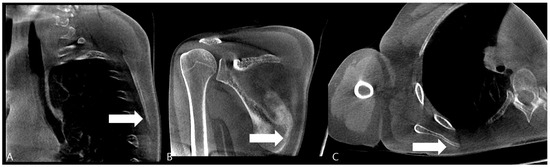

Figure 3. Computed Tomography (CT) of the Right Scapula. (A) Cortical breakage and callus formation are observed on the medial side of the scapular in the sagittal image (white arrow). (B) Callus formation (white arrow) and periosteal reaction are observed on the inferior part of the scapular medial border in the coronal image. (C) Callus formation is observed on the scapula medial border in the axial image (white arrow).

Over a two-month follow-up period, the patient showed a gradual increase in punching power, and discomfort in the scapular region improved. At the three-month follow-up, a computed tomography (CT) scan of the right scapula was obtained to confirm the sonographic diagnosis. The CT images clearly revealed a cortical break with associated periosteal reaction at the medial border of the scapular body, corresponding precisely to the site of sonographic irregularity and point tenderness, thus definitively confirming the diagnosis of a stress fracture (Figure 3).